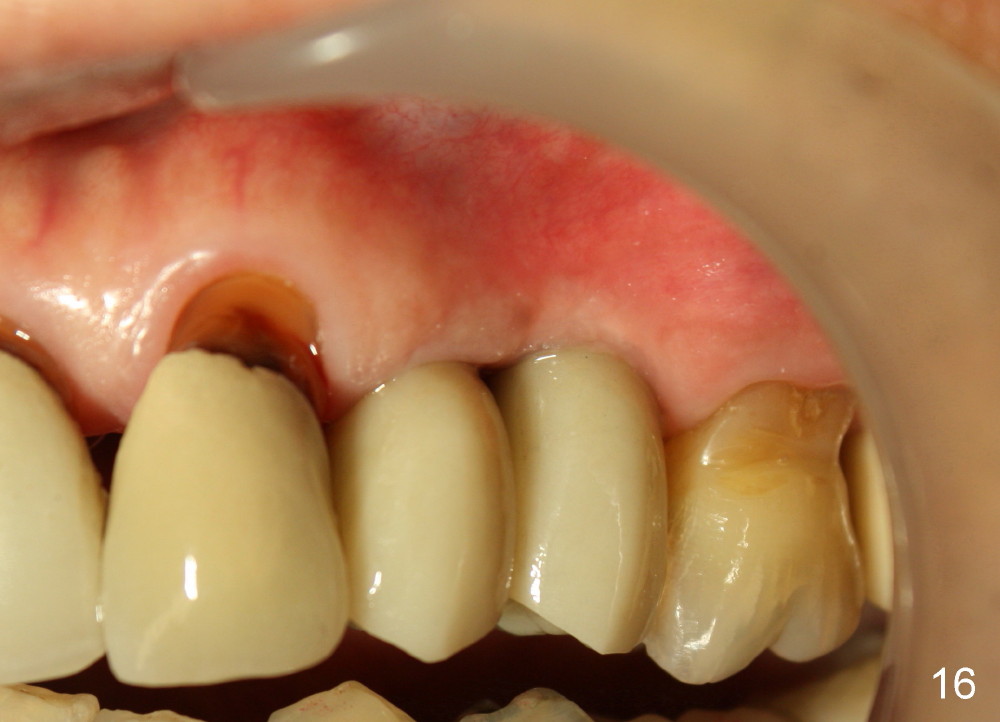

Three month follow-up shows that the gingiva and bone heal around these two implants (Fig.13-15). Crowns are cemented 4.5 months postop (Fig.16). There is no or minimal bone loss 9 months post cementation (Fig.17, as compared to Fig.15). The bone is stable around the implants 18 months post cementation (Fig.18 panoramus). Root canal therapy is done at #14 between the last follow up appointments.